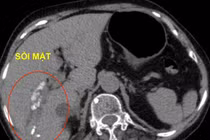

Phương pháp xử lý tán sỏi đường mật qua da bằng laser được Trung tâm Tiêu hóa – Gan mật áp dụng là một đột phá với kỹ thuật xâm lấn tối thiểu, bảo tồn được túi mật nên bảo toàn được chức năng tiêu hóa và giúp quá trình hồi phục của bệnh nhân nhanh chóng.